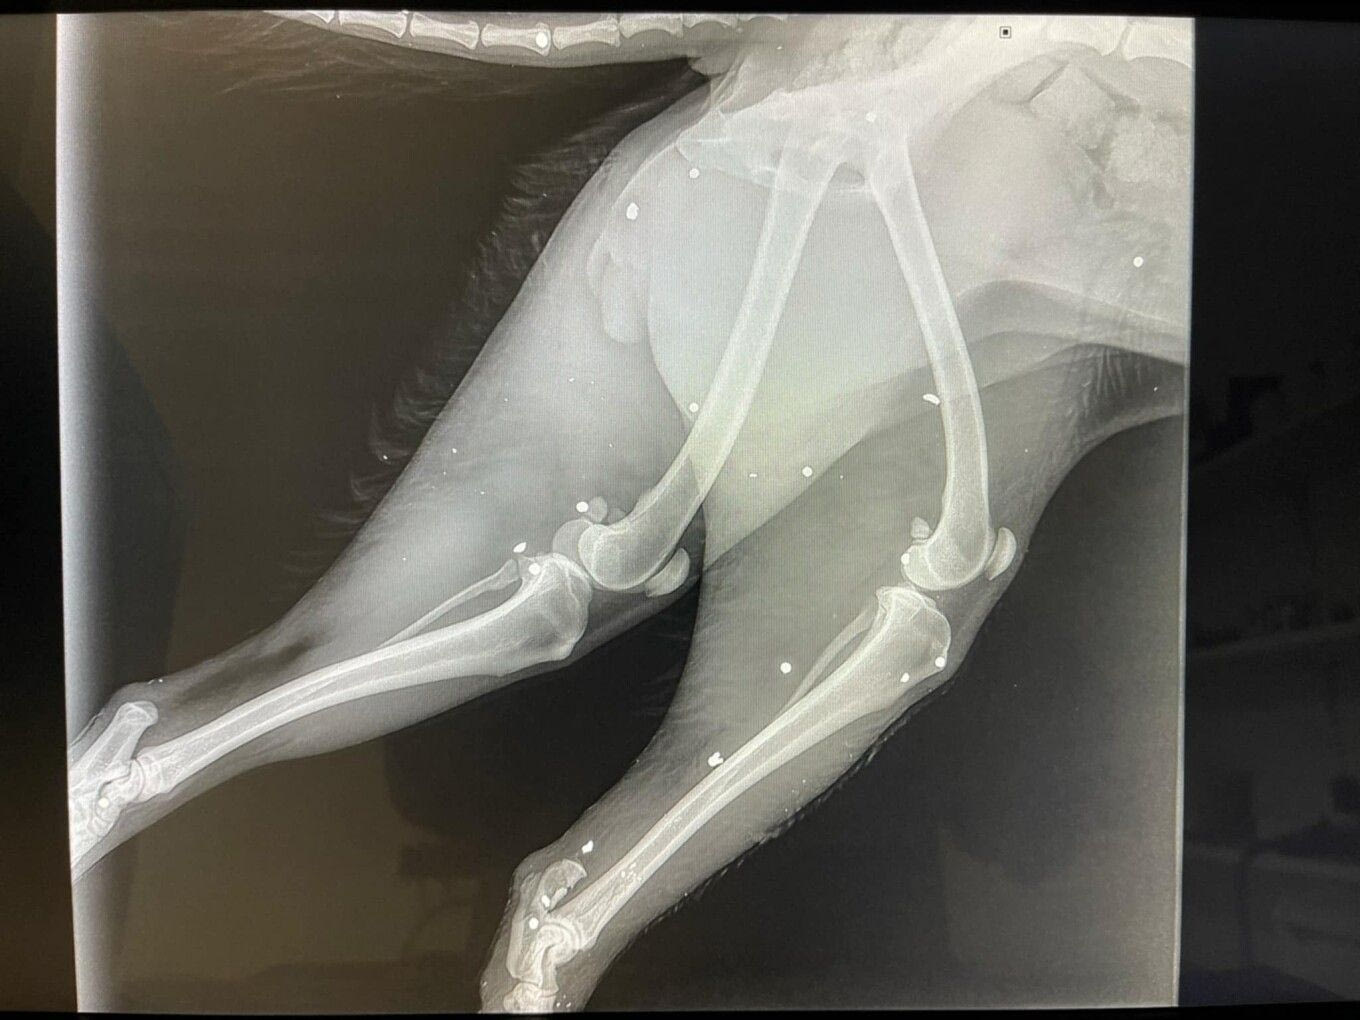

Σύμφωνα με όσα αναφέρει, άγνωστος φέρεται να ξυλοκόπησε και να πυροβόλησε το ζώο, το οποίο εντοπίστηκε σοβαρά τραυματισμένο στην άκρη του δρόμου.

Παρά τις προσπάθειες των κτηνιάτρων, χρειάστηκε ακρωτηριασμός ενός ποδιού.